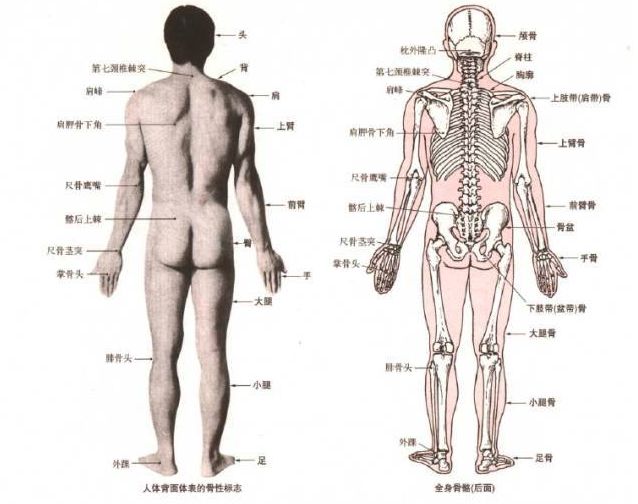

4、体态自我评估方法人的动作可以在三个动作面上进行,即矢状面、冠状面和 水平 面,如下图所示:

观察人的身体有 4 个角度:正面、背面和两个侧面,不同的角度观察的 内容 不同,也因此能发现不同的体态问题。

体态观察点

体态观察是通过几个关键的解剖点的排列来判断体态表现,常用的观察点请见下表。

注:上图中为了展示清楚,骨骼模型采用解剖学站姿,实际做体态观察时, 手臂 自然下垂即可。